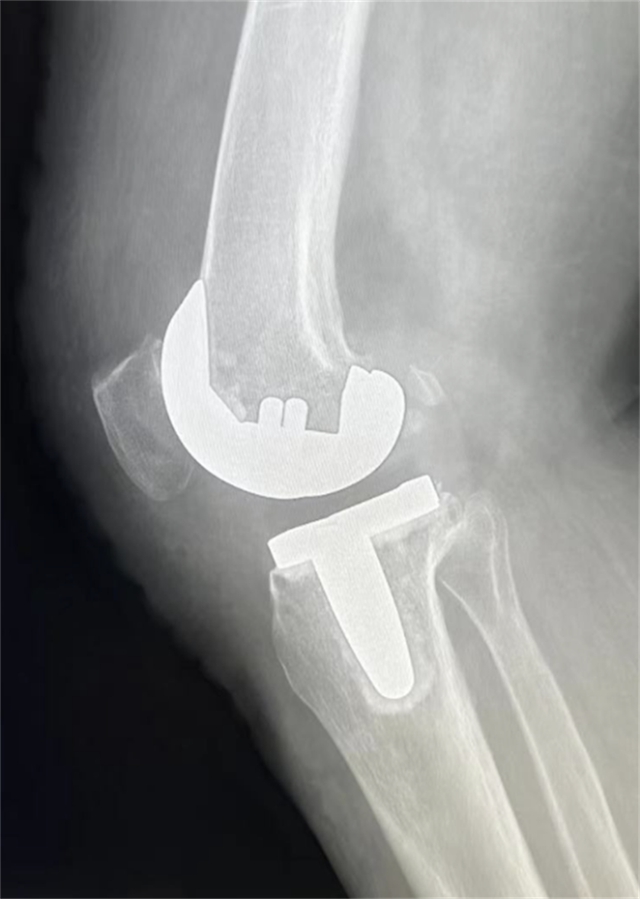

患者术后影像资料

患者术后第3天,膝关节可屈曲120°